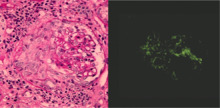

Crescentic glomerulonephritis induced by infective endocarditis on PAS staining and immunofluorescence. PAS staining (left) demonstrated circumferential and cellular crescent formation with interstitial nephritis. Immunofluorescence (right) demonstrated C3 positive staining in mesangial area.

Photomicrograph of renal biopsy showing crescent formation and tuft narrowing. Periodic acid silver methenamine stain.

Rapidly progressive glomerulonephritis, also known as crescentic GN, is characterised by a rapid, progressive deterioration in kidney function. People with rapidly progressive glomerulonephritis may present with a nephritic syndrome. In management, steroid therapy is sometimes used, although the prognosis remains poor.[8] Three main subtypes are recognised:[4]:557–558

Histopathologically, the majority of glomeruli present "crescents". Formation of crescents is initiated by passage of fibrin into the Bowman space as a result of increased permeability of glomerular basement membrane. Fibrin stimulates the proliferation of endothelial cells of Bowman capsule, and an influx of monocytes. Rapid growing and fibrosis of crescents compresses the capillary loops and decreases the Bowman space, which leads to kidney failure within weeks or months.